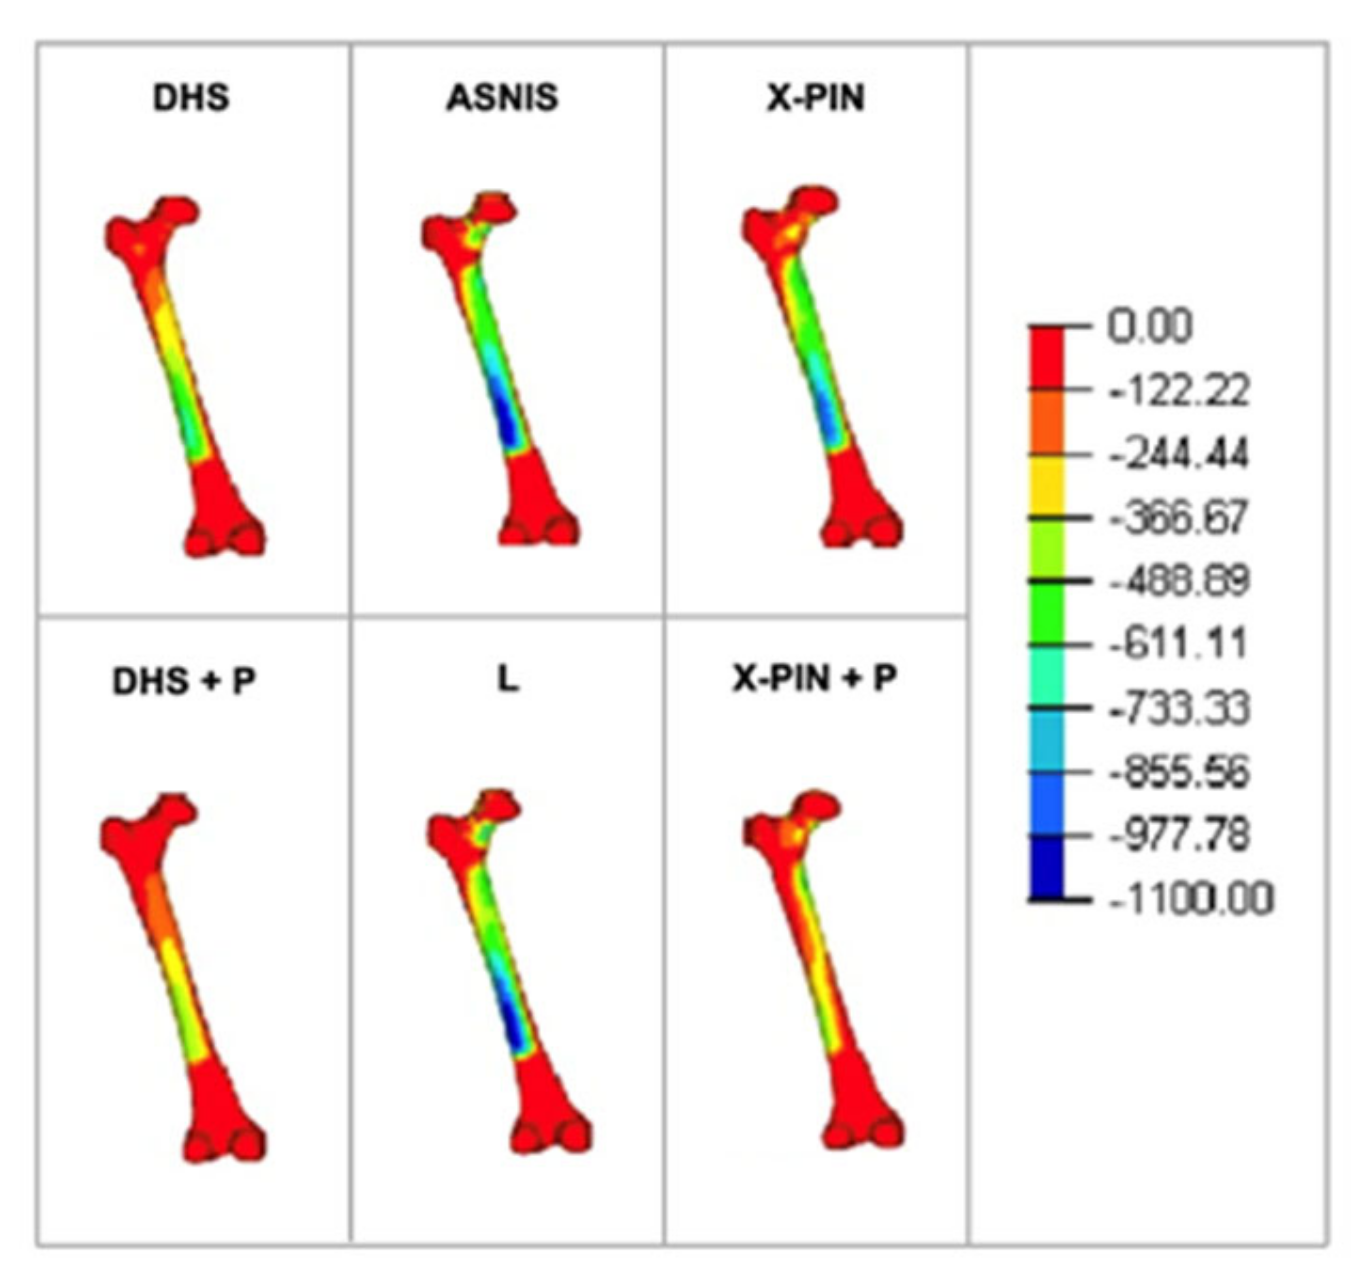

3. Results

4. Discussion